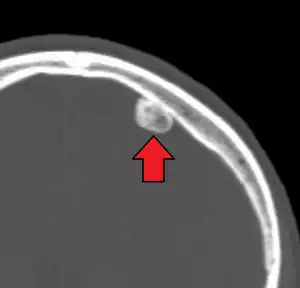

Osteogenic tumors, also known as bone forming tumors, are a type of bone tumor that can be non-cancerous (osteoma and osteoid osteoma), intermediate or locally aggressive (osteoblastoma), or cancerous (osteosarcoma).[1][2] There are ten subtypes and they are easier to distinguish than chondrogenic tumors.[1][2]

| Non-cancerous | Osteoma |

| Osteoid osteoma |